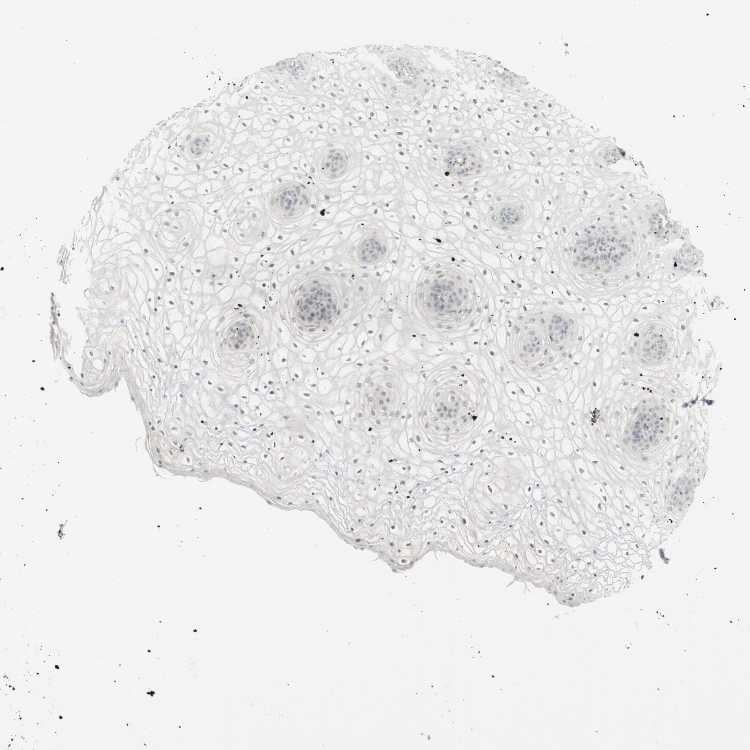

VAGINA - Antibody stainingi

Antibody staining in the annotated cell types in the current human tissue is reported as not detected, low, medium, or high, based on conventional immunohistochemistry profiling in selected tissues. This score is based on the combination of the staining intensity and fraction of stained cells.

Each image is clickable and will lead to virtual microscopy that enables deeper exploration of all samples and also displays staining intensity scores, fraction scores and subcellular localization as well as patient and tissue information for each sample.

Antibody HPA011070

Squamous epithelial cells Not detected